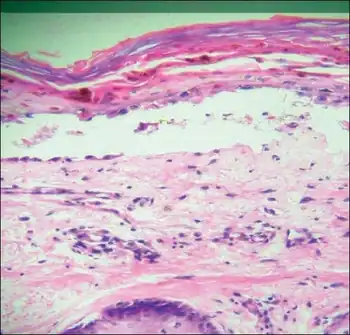

Transfusion associated graft versus host disease -Mononuclear cell infiltration and inflammation of affected epithelium, with focal vacuolation of basal epithelial cells | |

TA-GvHD can be suspected from a biopsy of the affected skin or liver,[3] and established by HLA analysis of the circulating lymphocytes. This testing can identify circulating lymphocytes with a different HLA type than the tissue cells of the host.